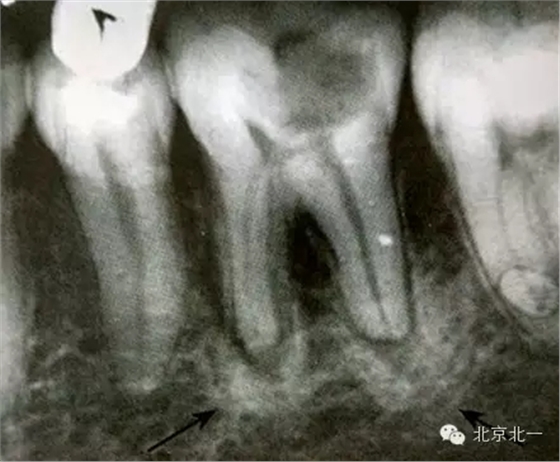

根尖片顯示D6深齲,根尖低密度區(qū)周圍骨小梁增粗、增多,骨質(zhì)密度增高,骨髓腔變?。ê谏^)。